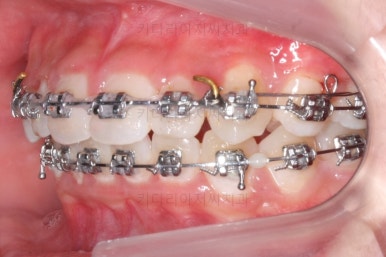

이번에 사용한 장치는 메탈장치였고, 치료 초기에는 매복치를 제대로 꺼내는데 초점을 맞췄어요.

처음 장치를 부착한 이 후 8개월이 흐른 시점이네요. 꽤나 오랫동안 천천히 송곳니를 가지런하게 해줘요.

치료 10개월째의 모습입니다.

이정도면 다 끝난 것 같은 느낌이 드시지 않나요? 과개교합도 개선시켰고 매복치아 덧니도 가지런하게 했어요.

마무리 때의 모습입니다.

치아는 매우 가지런해졌고 뾰족하던 앞니의 형태도 좋아졌어요.

매복되어 있던 송곳니도 잘 나왔고 과개교합도 물론 개선이 되었습니다.